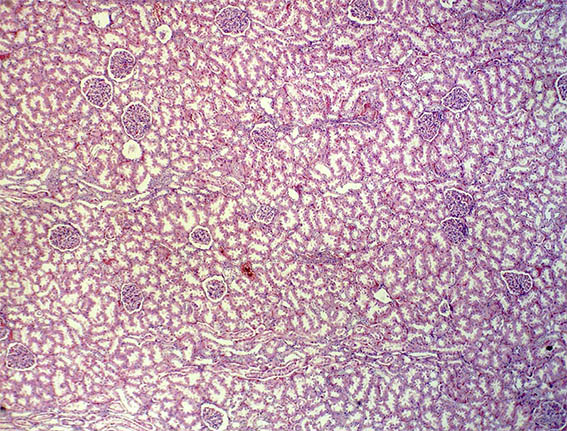

Figura 1. H&E, X100.